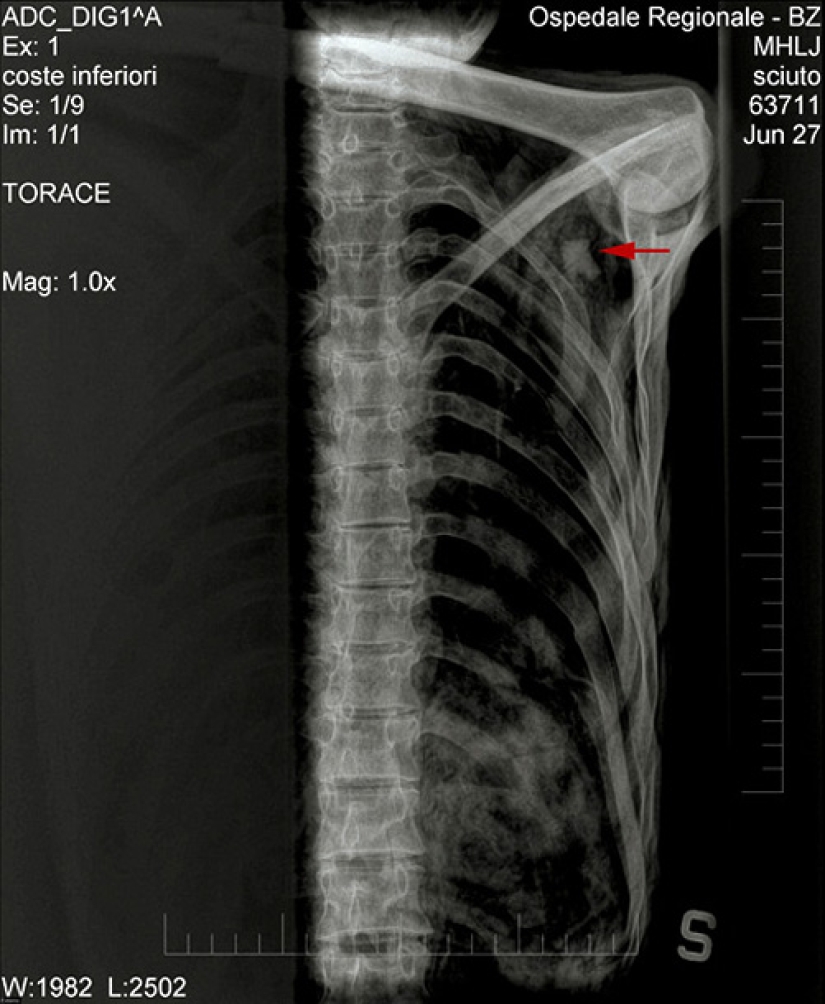

El Dr. Edward Egarter Wigl y sus colegas están estudiando una punta de flecha clavada en el hombro de Etzi. Alguien le disparó a Etzi por la espalda hace más de cinco mil años, la flecha atravesó tan profundamente el hombro que no fue posible obtener la punta de Etzi.

La flecha roja en la imagen de rayos X marca la ubicación de la punta de flecha.